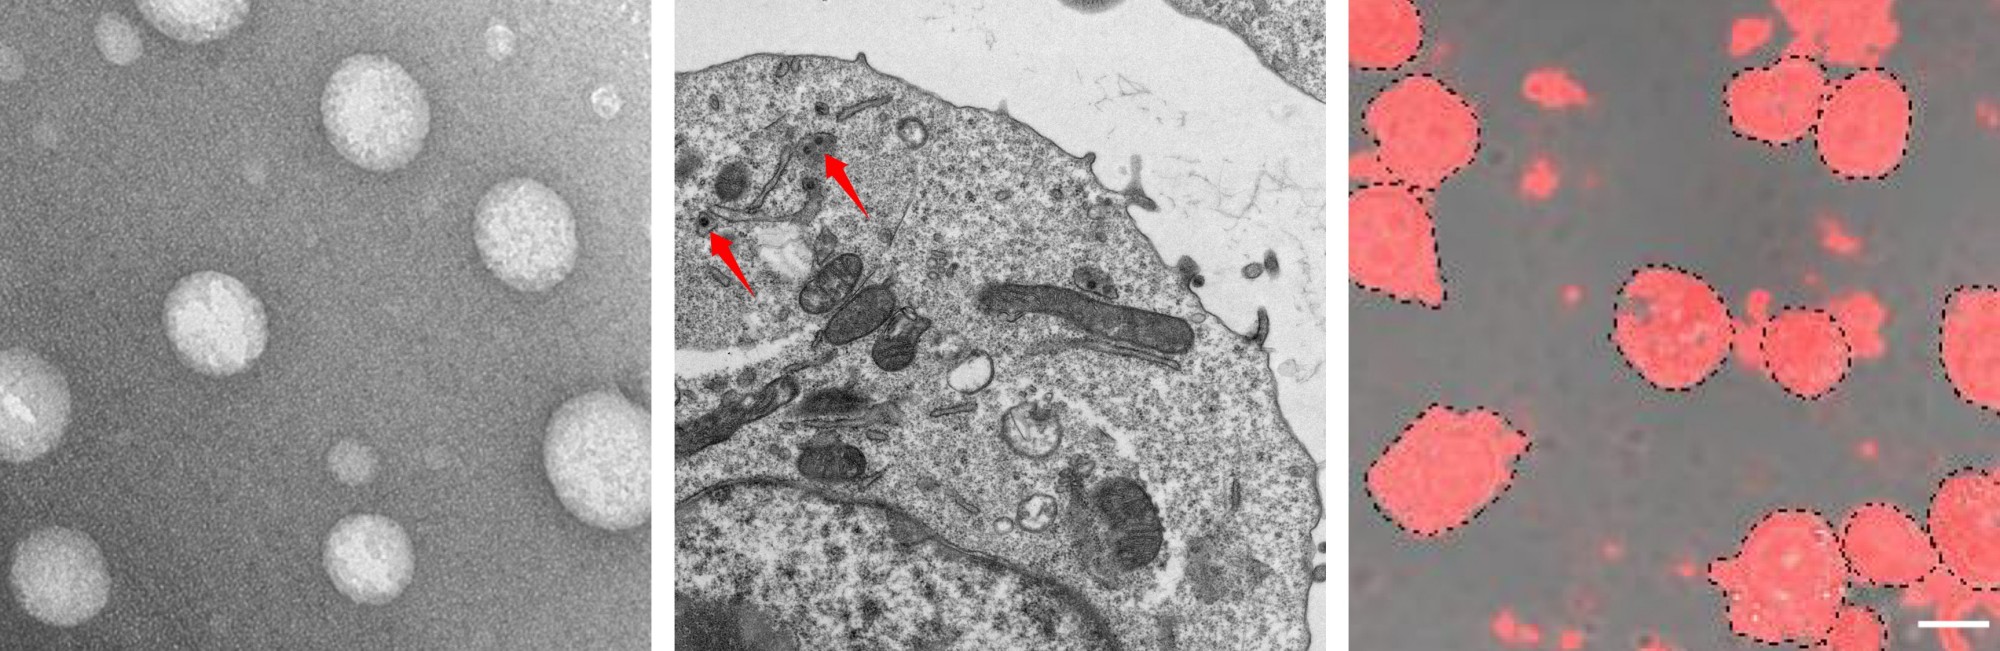

Development of nanocarrier-based systems for in situ gene editing and precision-targeted immune cell engineering, with therapeutic applications in cancer and autoimmune diseases.

• Nanoshuttles Simulating Phagocytosis of Apoptotic Cells

• Zombie Macrophage-Encapsulated Responsive Nanoparticles

• Nanomaterial Cellular Hitchhiking